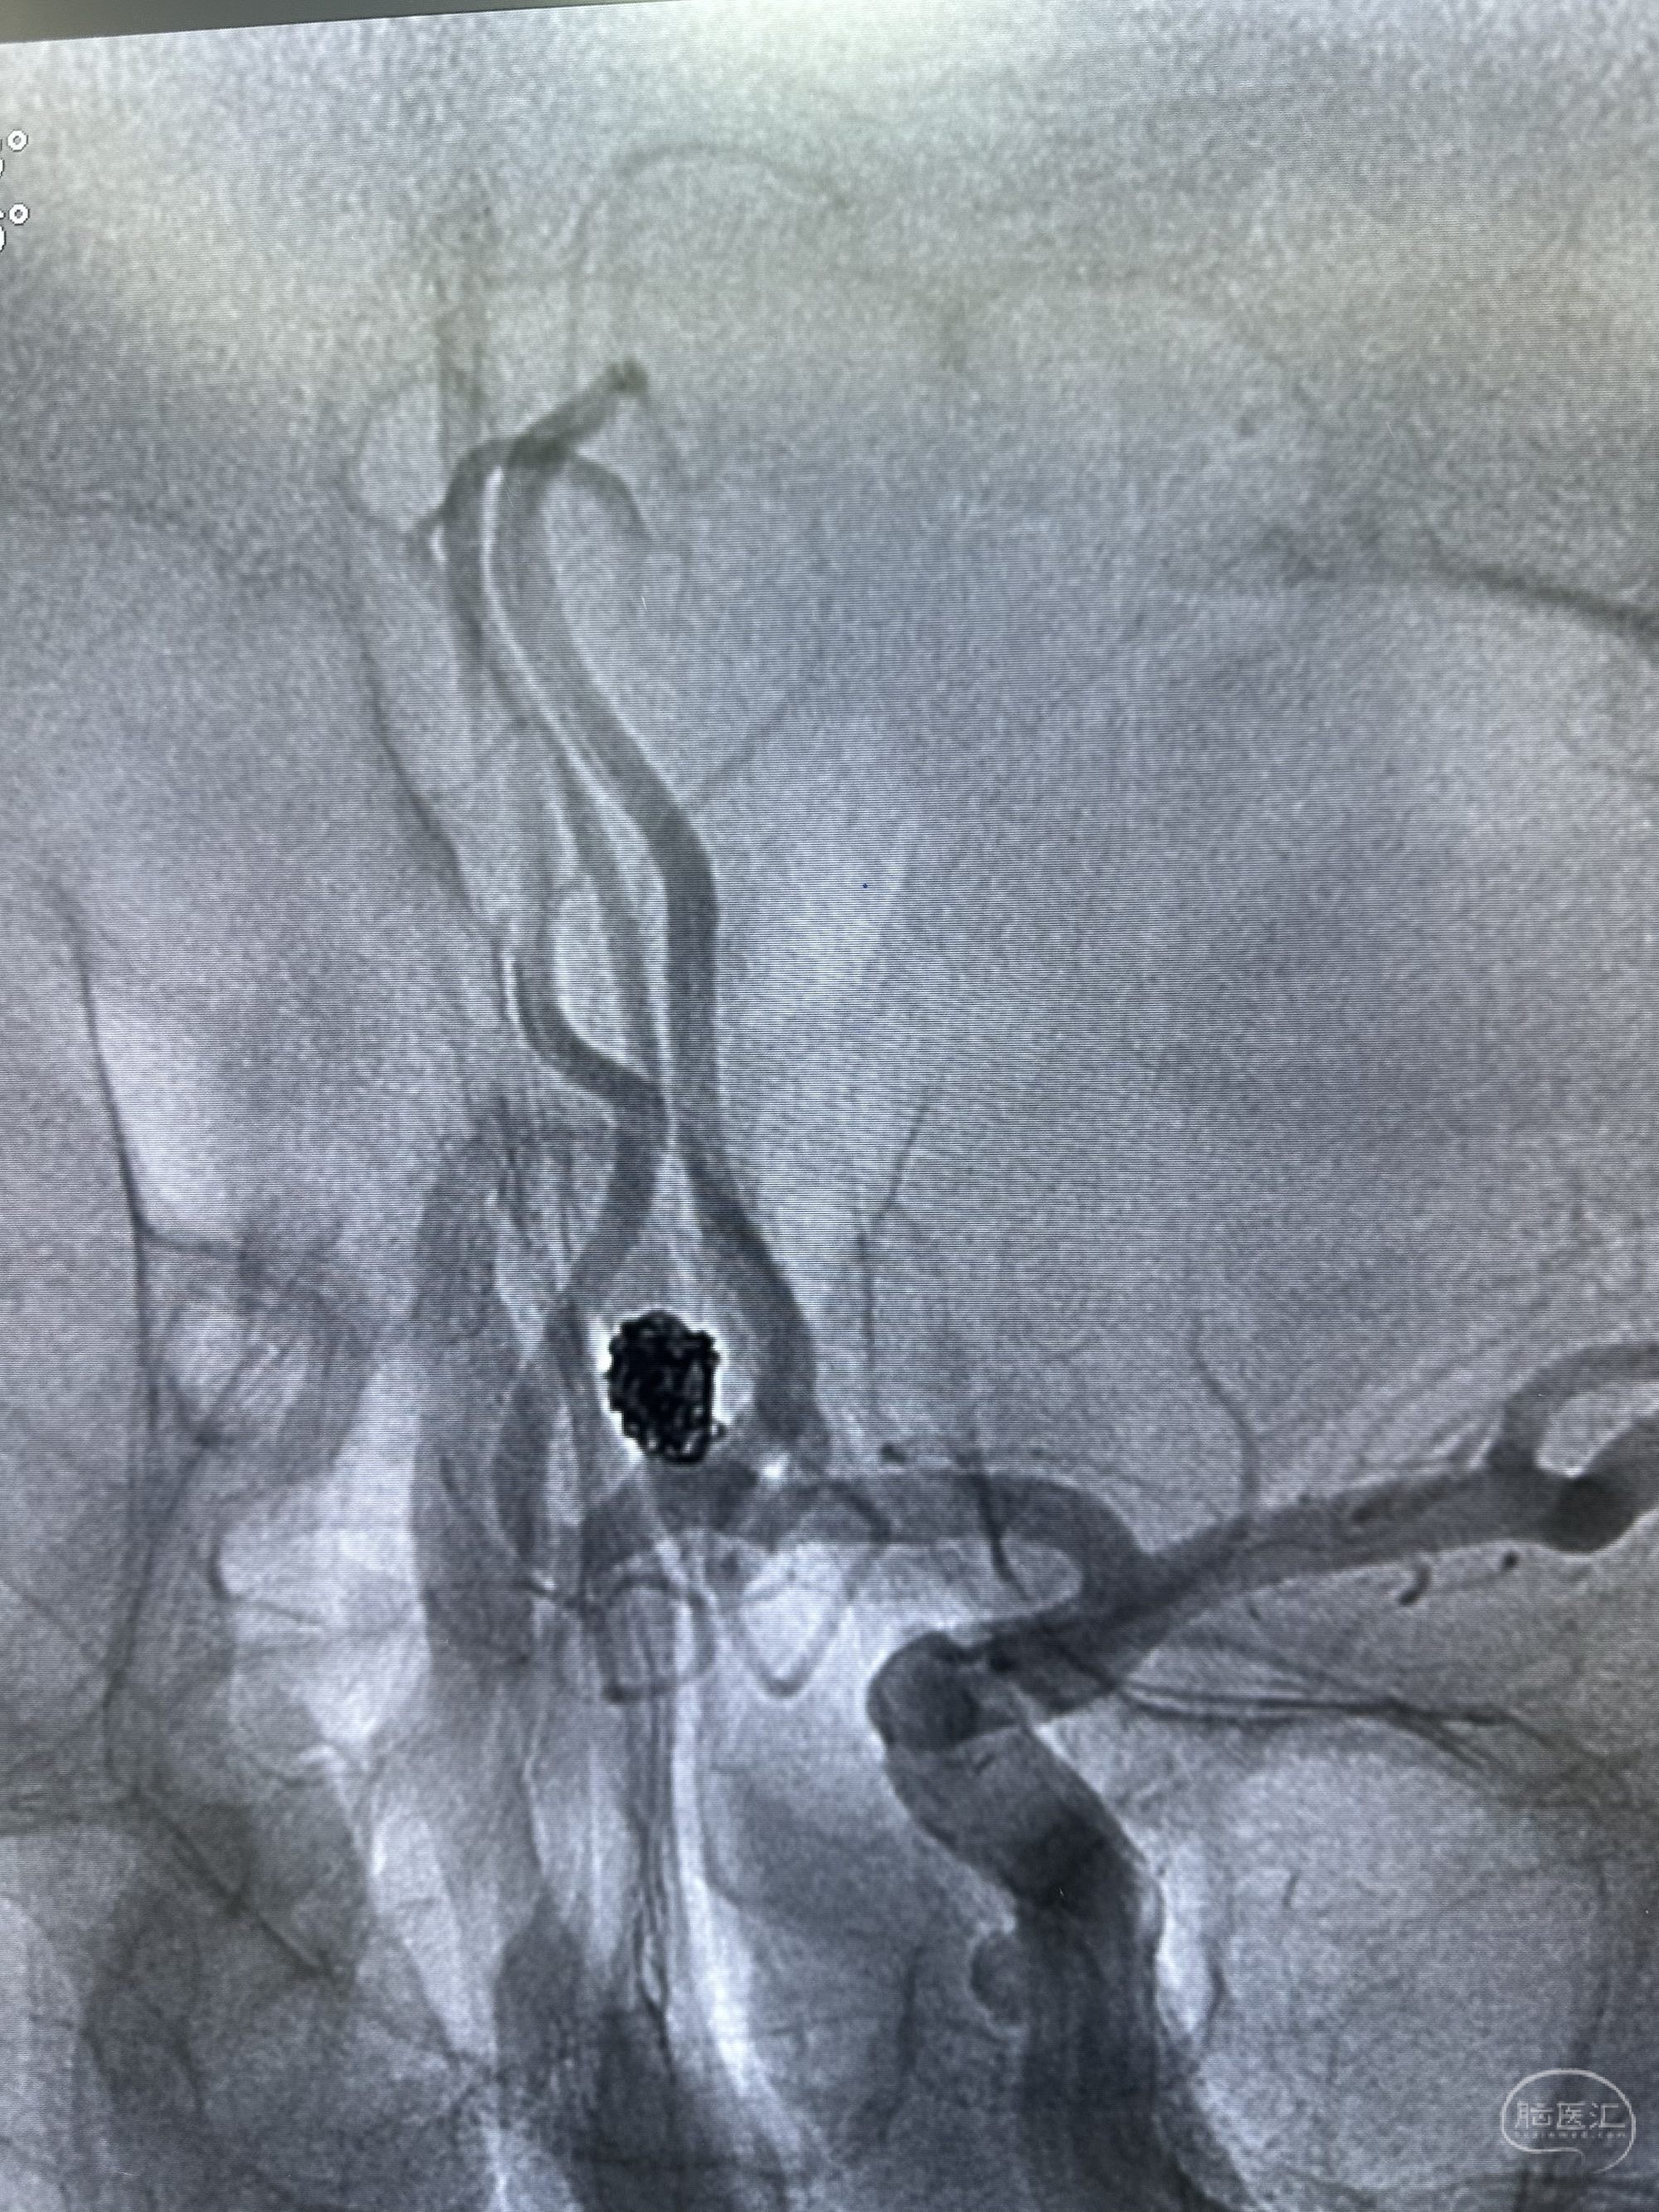

第一枚圈选择4*8的target 3D

圈的形态

后续填塞三枚ES 3*8,1.5*3,1*3.

最后圈的形态